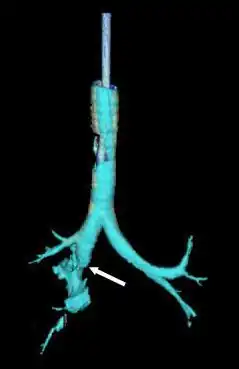

| Reconstrução da traqueia e brônquios com tomografia computadorizada mostrando o rompimento do brônquio principal direito com lucência anormal (seta)[1] | |

A radiografia de tórax é a técnica inicial de imagem usada para diagnosticar a lesão traqueobrônquica.[17] A imagem pode não mostrar sinais em pacientes assintomáticos.[15] Indicações de lesão traqueobrônquica em radiografias incluem deformidade na traqueia ou defeito na parede traqueal.[17] Radiografias também podem mostrar enfisema cervical, ar nos tecidos do pescoço.[2] Raios X podem revelar lesões associadas e sinais como fraturas e enfisema subcutâneo.[2] Se o enfisema subcutâneo ocorre e o osso hioide aparece em uma radiografia posicionado anormalmente alto na garganta, pode indicar que a traqueia foi seccionada.[4] A lesão traqueobrônquica também é suspeita se um tubo traqueal aparece deslocado em uma radiografia, ou se seu balonete parece mais cheio que o normal ou protrai através de um rasgo na via aérea.[17] Se um brônquio é completamente rasgado, o pulmão pode colapsar para fora, em direção à parede torácica (em vez de para dentro, como no pneumotórax usual), pois perde a fixação ao brônquio que o mantém centralizado.[6] Em uma pessoa deitada de costas, o pulmão colapsa em direção ao diafragma e às costas.[23] Esse sinal, descrito em 1969, chamado sinal do pulmão caído, é patognomônico [en] da lesão traqueobrônquica (diagnóstico exclusivo, pois não ocorre em outras condições); no entanto, é raro.[6] Em até um em cinco casos de trauma contuso com lesão traqueobrônquica, não há sinais na radiografia torácica.[23] A tomografia computadorizada detecta mais de 90% das lesões traqueobrônquicas por trauma contuso,[3] mas nem raios X nem tomografia substituem a broncoscopia.[6]